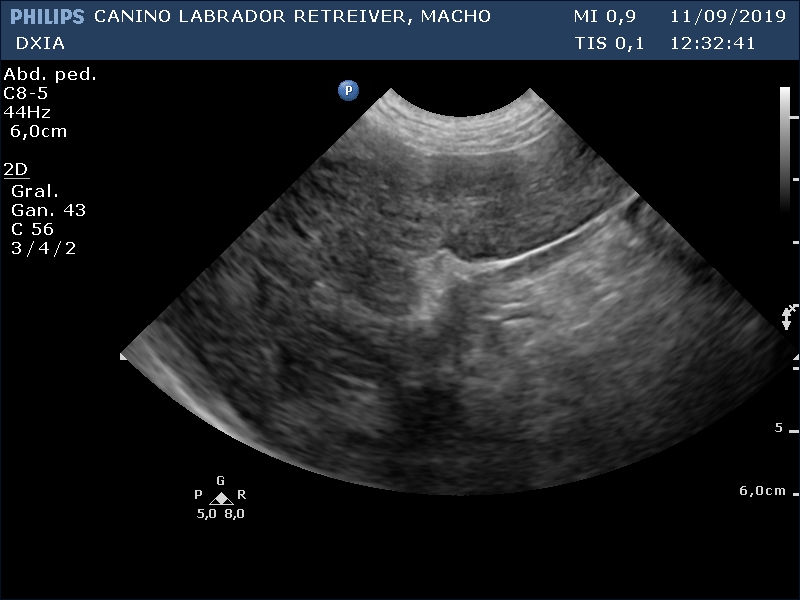

Ecografía Abdominal DXIA Scott

Lóbulo hepático.

Parénquima hepático homogéneo en lóbulos caudal a la vesícula biliar y lóbulo derecho próximo al estómago, pero en el resto del hígado se observa hepatomegalia (al presentar bordes hepáticos redondeados) junto con patrón marcado nodular que le da heterogenicidad. Se realiza PAF ecoguiada para su posterior análisis anatomopatológico, pero si no es suficiente la muestra se requerirá la realización de biopsia.

Vesícula biliar con pared fina e hiperecogénica. No presencia de barro biliar.